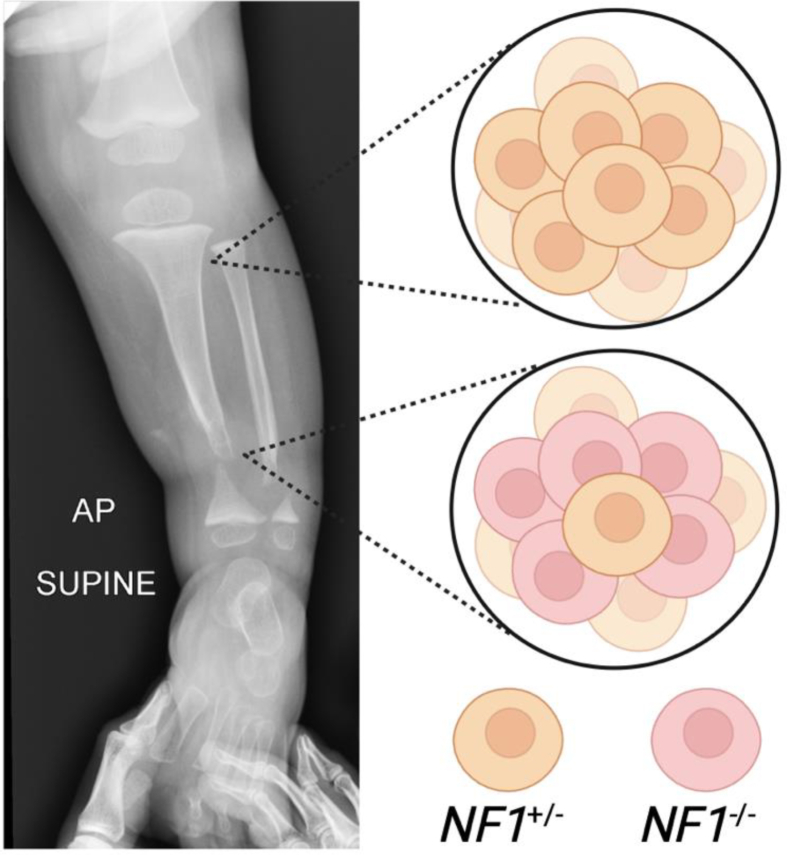

Neurofibromatosis Type 1 (NF1) is a tumor-predisposition syndrome caused by heterozygous mutations in the NF1 gene. In addition to oncologic manifestations, individuals with NF1 face a heightened risk of developing secondary skeletal complications associated with somatic loss-of-heterozygosity. Long bone dysplasia and post-fracture pseudarthrosis are among the earliest skeletal manifestations observed in children with NF1. Most commonly occurring in the tibia, pseudarthroses are often treated with a combination of resection, fixation, bone grafting, and rhBMP2. Although rates of initial union are reported to be high, the risk of re-fracture and subsequent pseudarthrosis is similarly elevated, and some patients may ultimately require amputation. Basic science research related to NF1 pseudarthrosis is uncovering the cellular pathogenesis of the disease and unlocking new potential treatment paradigms. Here, we review the current understanding of the biological etiology of NF1 pseudarthrosis, informed by molecular studies of patient-derived tissue samples and mechanistic studies utilizing pre-clinical mouse models. Results from these studies are presented within the context of contemporary treatment paradigms. Finally, we introduce novel treatment paradigms currently under investigation in pre-clinical models and discuss how these may potentially translate to improve surgical outcomes in children with NF1 pseudarthrosis.

Key concepts: (1)Fracture pseudarthrosis in patients with NF1 is caused by somatic mutations in the NF1 gene.(2)Somatic NF1 gene mutations hyperactivate the MAPK signaling pathway, disrupting cellular mechanisms necessary for proper fracture healing.(3)Emerging therapies aim to target hyperactive MAPK signaling to promote fracture healing by fostering osteogenic instead of fibrogenic pathways in skeletal progenitor cells.